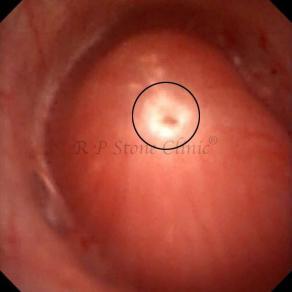

Kidney stone is a solid mass of CRYSTALS. It is the process of crystallization which initiates the formation of kidney stones. This happens in nephrons or units of kidney. Once a small crystal is formed, it can both grow & unite with other crystals leading to the formation of small concretion which eventually forms a stone. Once these large crystals detach from the collecting ducts, the process of stone formation starts in the renal collecting system. A recurrent kidney stone former is advised to know a little bit about something known as Randall’s plaque. Alexander Randall discovered plaques on the renal papillae eight decades back based on examination of 1154 pairs of autopsied Kidneys. He described these renal papillary lesions as cream colored or milk patch areas composed of calcium phosphate & calcium carbonate. These plaques could act as NIDUS for formation of KIDNEY STONE. Calcium Oxalate stone can form on this nidus & then detaches from this plaque to become a free floating stone in the collecting system of kidney

These images are taken as snap shots from the video recording of RIRS Surgery done at our hospital. These are Randall’s Plaques seen with Digital FLEX XC & Digital FLEX XC S. The cream or whitish patches are seen on the tips of RENAL PAPILLAE as seen in images below.